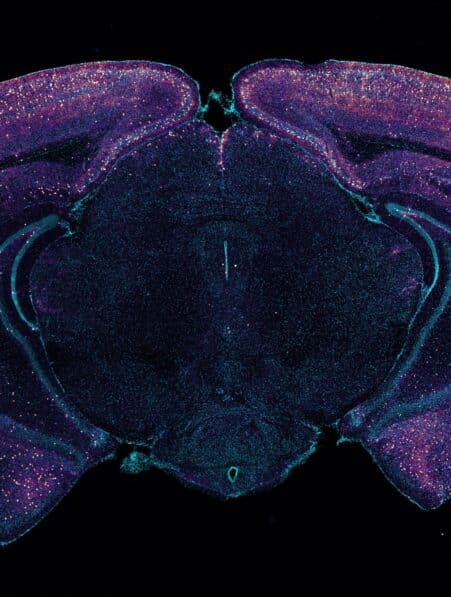

Alzheimer : l’accumulation de graisse dans les cellules cérébrales pourrait en être la cause majeure

On sait désormais au moins qu’un mélange complexe de divers facteurs est à l’origine de la maladie d’Alzheimer… L’âge, la...